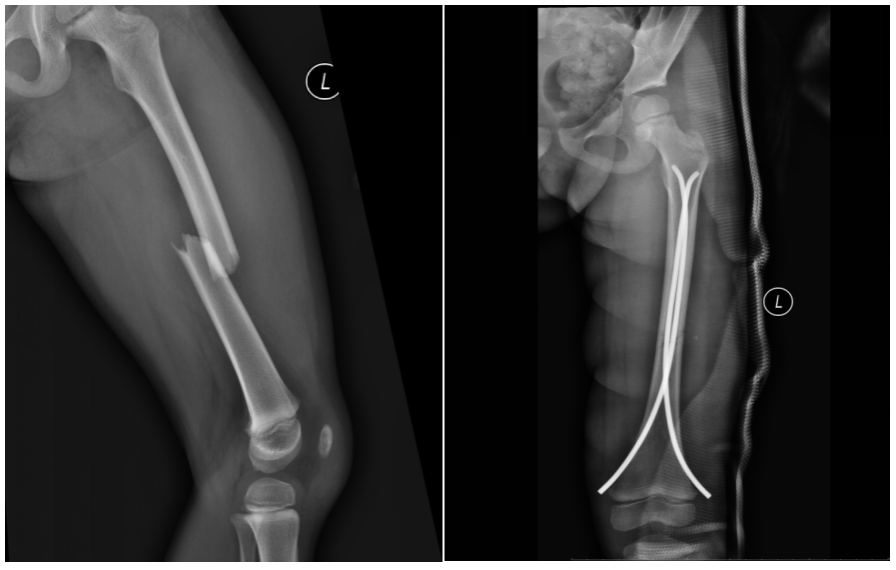

1.小儿骨折微创手术治疗:

治疗范围:儿童股骨骨折、胫腓骨骨折、肱骨骨折及尺桡骨骨折。

微创手术治疗:微创手术采用闭合复位,具有手术切口小、软组织损伤小、手术时间段、术后康复快、住院时间短及并发症少等优点,给早期锻炼和康复带来了条件和机会。

弹性髓内针治疗:是儿童长骨骨折的一种有效方法,具损伤小、不干扰骨折断端局部血运、不损伤骨骺、患肢功能恢复快及并发症少等优点。